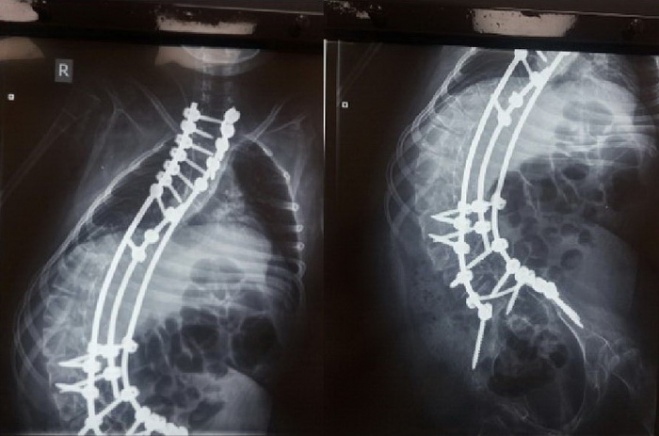

Операция Арине была сделана 16 мая и прошла успешно! Сейчас мы на домашней реабилитации. Швы заживают, болит спинка но Арина терпит!

Поставили нам неутешительный диагноз – остеопороз. Теперь на ближайшие 3-5 лет лечение. Хирурги наши просто Волшебники и сделали невозможное – Арина теперь с почти ровной спинкой, и самое главное – дышит сама. Мы очень переживали за ее легкие дыхание и сердце .

Вы бы ее не узнали сейчас – высоченная красотка, в росте примерно плюс 20 см.